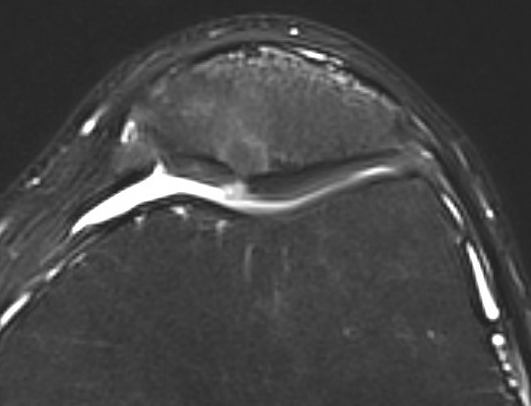

MRI

- maltracking

- patella tilt / Lateral patella pressure syndrome

Maltracking

Tight lateral retinaculum